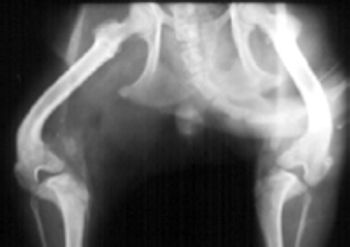

CHD has been called inherited, a developmental disease, and most accurately in the author's opinion, a "moderately heritable disease". CHD is a multifactorial disease with part of its cause being from genetic influences (estimated at 25%-80%) and part from environmental influences.

At birth most hips are normal. The femoral head and neck are cartilaginous and begin forming bone by endochondral ossification.